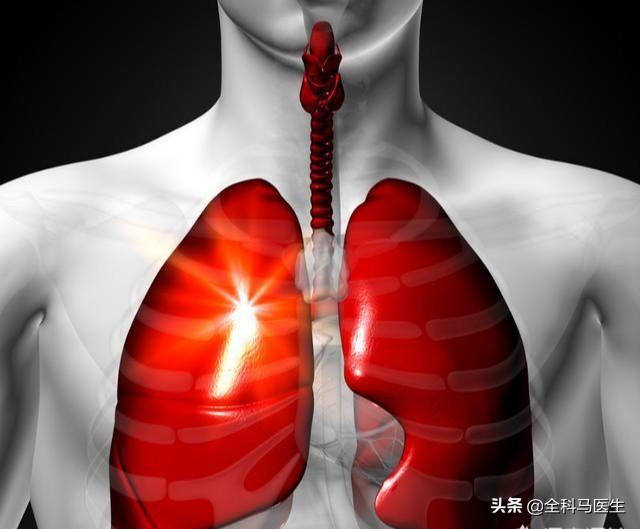

過敏な空咳

咳は、肺や気管支の病変の明らかな現れである。 刺激性の乾いた咳がある場合は、気管支の粘膜に腫瘍が成長している可能性があり、気管支中心性肺がんの初期症状である。 この感覚は、気道に米粒を詰まらせるようなもので、私たちの身体はストレスで反応し、コントロールできない咳が起こる。

しかし、咳は痰を伴わないか、痰が少ない傾向があり、乾いた咳として現れ、日中は頻繁に咳き込み、夜間はベッドで不随意に咳き込む。

痰に血が混じる、または血を吐く

肺腫瘍組織が悪性に増殖し続けると、正常な肺組織を傷つけ続け、癌細胞が剥がれ落ちる際に炎症や出血が起こりやすくなり、痰に血が混じる現象がしばしば起こるようになる。腫瘍細胞がさらに肺の血管組織を傷つけると、出血を起こしやすくなり、今度は痰に血が混じるだけでなく、大量の喀血を伴って血を吐く現象が起こる。

胸部圧迫感、息切れ、呼吸困難

胸苦しさ、息切れ、呼吸困難は肺がんに比較的よくみられる症状で、これは主に肺腫瘍の悪性増殖によるもので、多くの正常な肺組織を損傷し、ガス交換に影響を与えるため、胸苦しさや息切れを引き起こしやすい。肺腫瘍がさらに大きくなると、気道の換気を妨げ、正常なガス交換に影響を与えやすくなり、肺の胸苦しさや息切れの症状を悪化させ、呼吸困難に陥りやすくなります。 初期の肺がんの胸痛は不規則で、一種の鈍痛です。胸痛がひどく耐え難い場合は、すでに肺がんの進行期に入っています。

胸痛

肺がんの初期には、胸の痛みは通常現れませんが、肺がんが中期や末期になると、腫瘍が成長し続けるため、神経を圧迫しやすくなり、胸に漠然とした痛みや鈍い痛みが生じます。また、肺の正常な組織もがん細胞によって常に傷つけられ、その過程で胸に漠然とした痛みが生じやすくなります。 胸の痛みがさらに強くなり、夜も眠れないほど痛く、日中も痛みに耐えられないような場合は、肺がんがすでに進行している可能性が高いです。